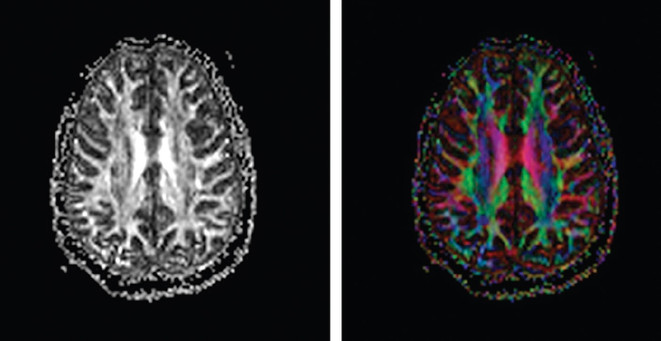

One of the most significant hurdles in treating mild traumatic brain injury (TBI) is that standard MRI scans frequently return "normal" results despite patients experiencing persistent, life-altering symptoms. The research highlighted in this episode explains that by oversimplifying patient groups, we often obscure the meaningful characteristics of brain injuries. By utilizing more sensitive sequences like diffusion tensor imaging, researchers can finally see the structural white matter changes that validate what veterans have been saying for years.

A key takeaway from the study is that the mechanism of injury determines the physical signature left on the brain. Blast exposures tend to impact the central white matter of the brain due to the unique physics of the pressure wave. In contrast, repetitive impact injuries often show changes in more peripheral gray matter structures. Understanding these differences allows clinicians to move away from a "one size fits all" approach and toward more accurate, personalized care.